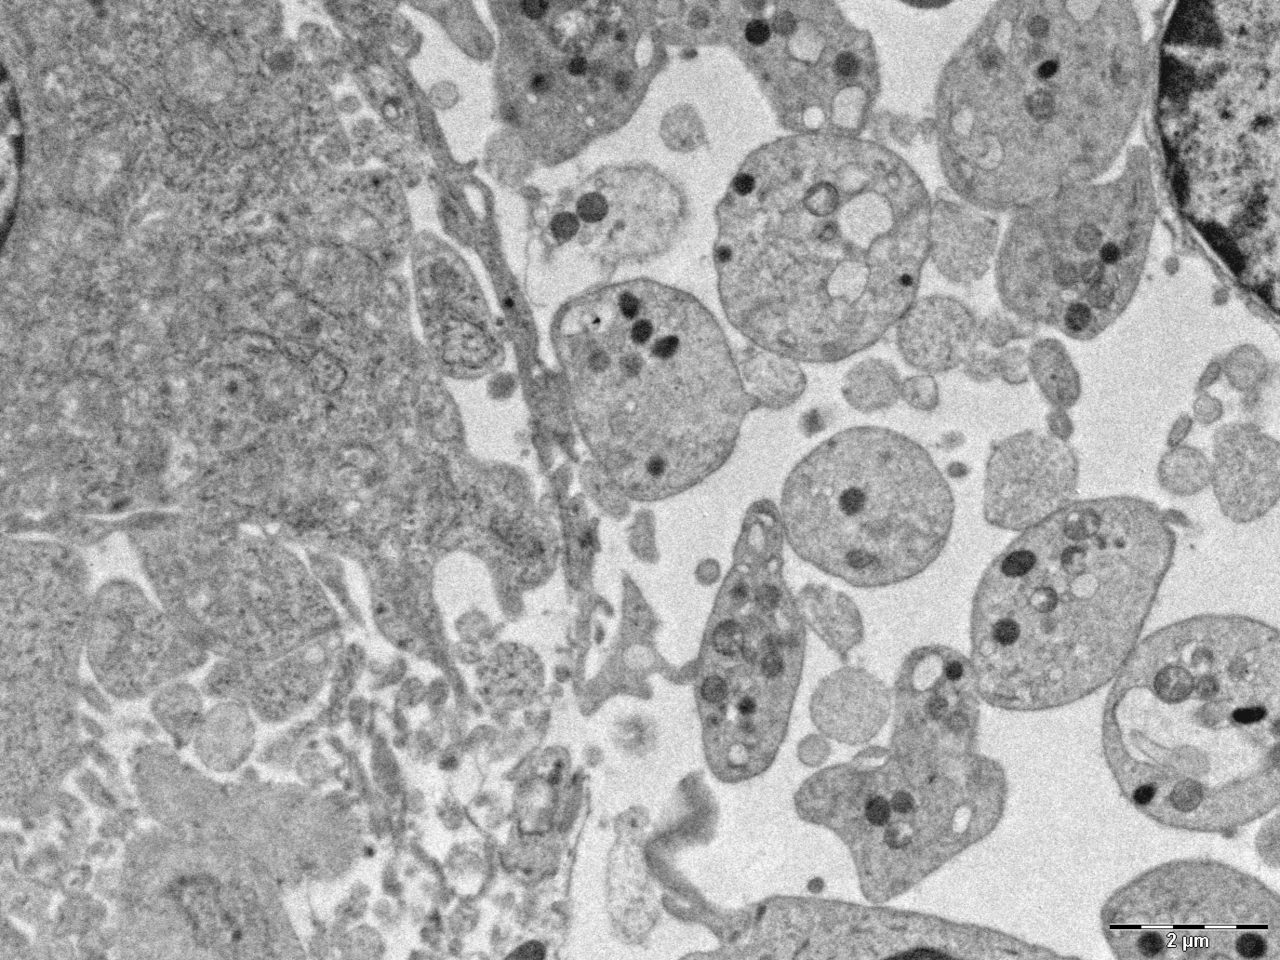

In aggregate, the CALRdel52 KI mice develop a more severe phenotype including thrombocytosis and progression to fibrosis than CALRins5 KI mice and in the homozygous than the heterozygous context. The amplification and competitive advantage of the HSCs were the strongest in homozygous CALRdel52 KI mice, as was the amplification of the megakaryocytic lineage. Heterozygous CALRins5 KI were almost undistinguishable from wt littermates and heterozygous CALRdel52 KI mouse phenotype was mild. Thus, heterozygous KI mice were developing a weaker disease than expected from mostly heterozygous CALRm patients. We ended up demonstrating that these differences between mouse and human were partly explained by a suboptimal activation of the murine MPL by the chimeric CALR mutants in our models. Indeed, using a luciferase assay we showed that chimeric CALR mutants like their human counterparts, are less potent to activate murine than human MPL. This also helped us understand why CALRdel52-induced fibrosis was so mild, as increasing MPL activation (using in vivo romiplostim treatment) significantly amplified the fibrosis. Another disconcerting point was the stronger thrombocytosis developed by CALRdel52 in comparison to CALRins5 KI mice, when the opposite seemed true in ET patients. One of our hypotheses was based on recent work highlighting that homozygosity is more frequent in CALRins5 than CALRdel52 in patients, suggesting the importance of a gene-dosage for CALRins5 oncogenic activity. We reasoned that although homozygous CALRins5 is frequently restricted to a small fraction of progenitors in patients, it might contribute to high level of thrombocytosis by for instance being specifically amplified in the MK/platelet lineage. Performing a competitive engraftment with limited amount of homozygous CALRins5 cells in presence of heterozygous CALRins5, we demonstrated that thrombocytosis increased above the level of mice engrafted with only heterozygous CALRdel52 cells, confirming a possible role of the homozygous clone in the disease severity.